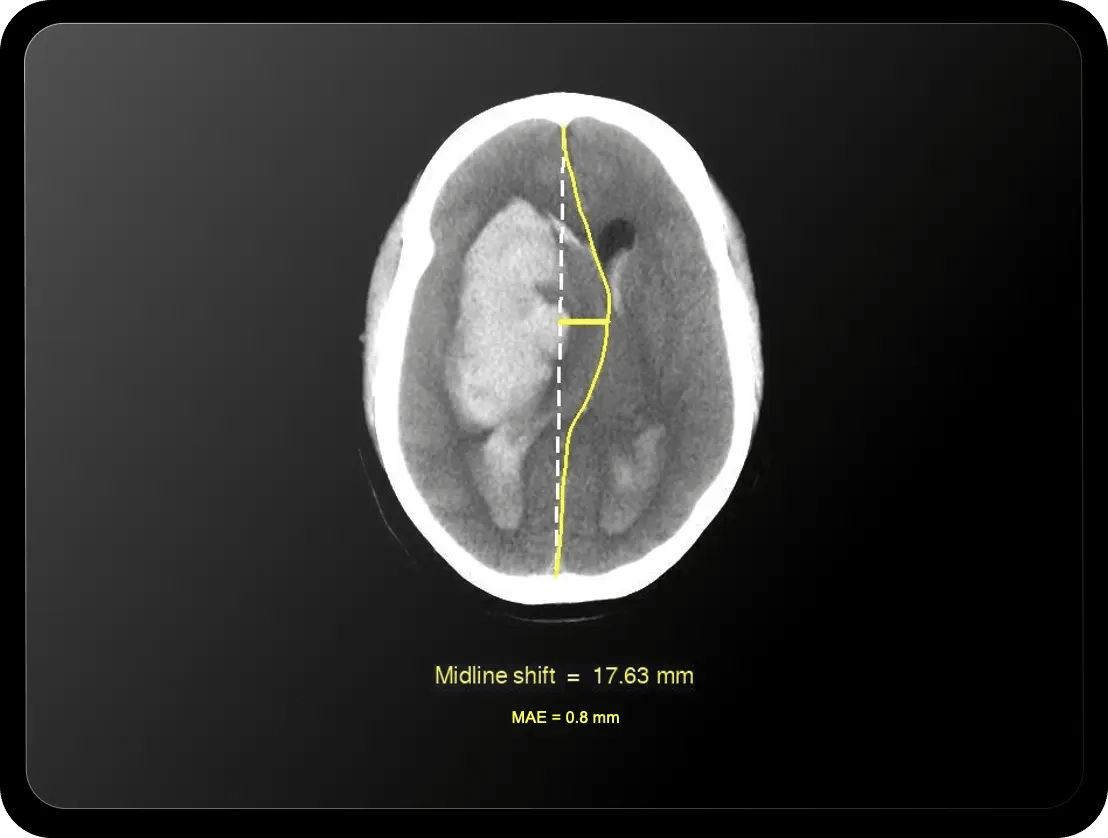

Quantify with confidence

Determine severity and volume of hematoma expansion with measurements down to 1 mL— supporting Joint Commission ICH score compliance